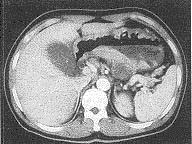

原发淋巴结外的非霍奇金淋巴瘤最常见的部位是()A.神经系统B.胃肠道C.呼吸道D.皮肤E.甲状腺

问题 原发淋巴结外的非霍奇金淋巴瘤最常见的部位是()

选项 A.神经系统 B.胃肠道 C.呼吸道 D.皮肤 E.甲状腺

答案 B